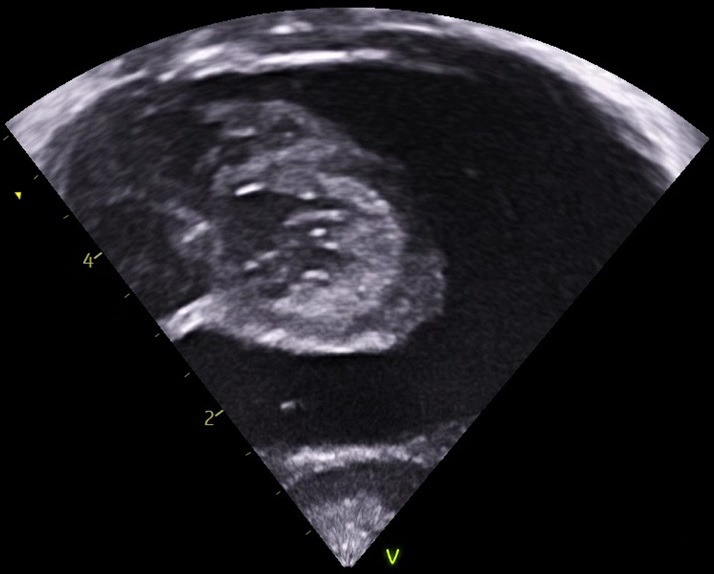

Infective atrial thrombus.